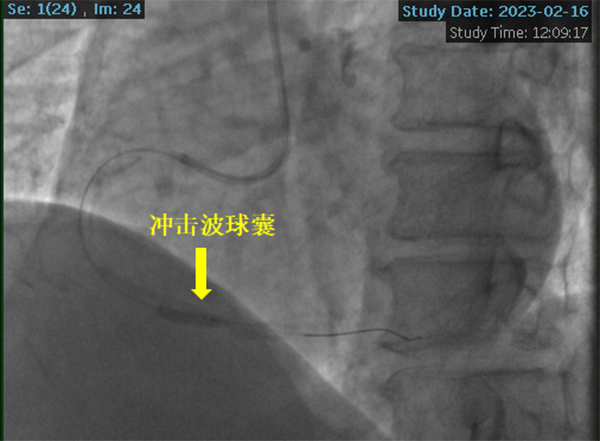

黃淮網(wǎng) 2023年2月16日,徐醫(yī)附院心內(nèi)科潘德鋒醫(yī)療團(tuán)隊(duì)率先于淮海經(jīng)濟(jì)區(qū)公立醫(yī)院成功開(kāi)展首例沖擊波球囊技術(shù)治療冠脈重度鈣化病變。術(shù)后患者癥狀明顯緩解,2月18日康復(fù)出院。

2023年2月16日,在副院長(zhǎng)楊煜的統(tǒng)籌指導(dǎo)下,心內(nèi)科冠脈專業(yè)專家組夏勇主任、徐通達(dá)主任、錢(qián)文浩主任、徐晤主任、陸遠(yuǎn)主任等針對(duì)病例進(jìn)行了充分的討論及術(shù)前準(zhǔn)備,由潘德鋒主任進(jìn)行手術(shù)操作。術(shù)中首先利用血管內(nèi)超聲明確患者冠狀動(dòng)脈的鈣化情況及血管直徑,在血管內(nèi)超聲的指導(dǎo)下,選擇了4.0mm×12mm的沖擊波球囊,順利送入沖擊波球囊至鈣化病變部位,釋放脈沖,每次釋放10個(gè)脈沖,最終通過(guò)釋放80個(gè)脈沖,將鈣化斑塊進(jìn)行了充分預(yù)處理,成功為患者植入了一枚冠脈支架,術(shù)后血管內(nèi)超聲顯示支架貼壁良好,患者癥狀明顯緩解,2月18日康復(fù)出院。